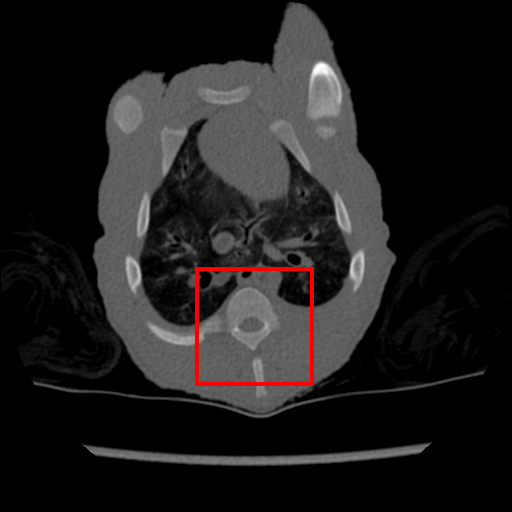

The same evaluation is performed for the supervised- and transfer-learning. Comparing with these two algorithms, it is clear that our approach delivers the highest PSNR. Although the results from transfer learning are closer, the difference is significant based on the t-test as we show in Sec. 4.4. Since this is the only experiment where we have access to a relatively large training set containing pairs of clean and real noisy data, we check the upper bound performance for our approach, which is the supervised learning performance using this large training set. Note that such full supervision violates one of our three assumptions mentioned in Sec. 1 – in particular, the one regarding the availability of a large number of training samples. Supervised learning achieves 40.28dB for and 38.84dB for , when trained with clean and real noisy training data. Our results in Table 1 indicate that we are close to this upper bound, although we train with synthetic training data. To further explore our approach, we meta-train it with clean and real noisy training data. Notably, our meta-denoising reaches 40.47dB for and 38.31dB for . This result shows the potential of meta-learning to become the standard training algorithm for the task of denoising. We present visual results in Fig. 1.